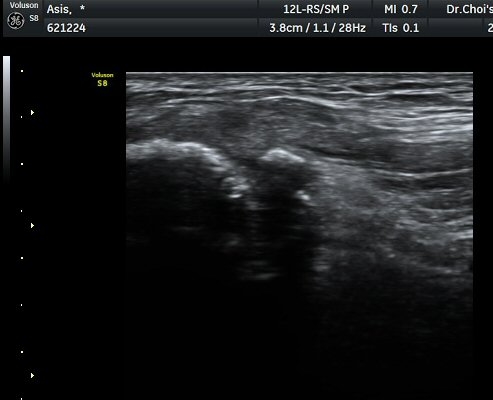

°üÂûµÇ°í(±×¸² 1) ¿ÜÃø´ëÅð±ÙÇǽŰæÀÇ ºÎÁ¾ÀÌ °üÂûµÊ(±×¸² 2, 3). Àü»óÀå°ñ±Ø Ⱦ´Ü¸é°Ë»ç¿¡¼­

°ß¿­°ñÀýµÈ °ñÆí°ú ¿ÜÃø´ëÅð±ÙÇÇ½Å°æ ºÎÁ¾ÀÌ °üÂûµÊ(±×¸² 4).